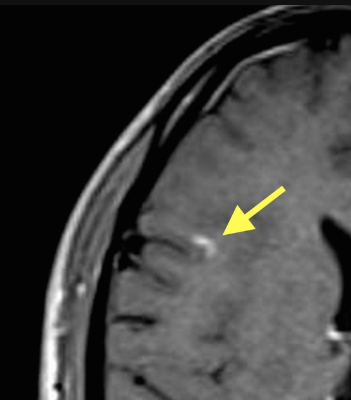

Right frontal lobe enhancing juxtacortical lesion. Source: Radiopedia

Bottom line: Look for periventricular, juxtacortical, infratentorial, and spinal cord lesions on T2 imaging. Gadolinium enhancement indicates active disease.

Brain imaging demonstrates multiple ovoid T2 hyperintense lesions in the periventricular region, oriented perpendicular to the lateral ventricles, consistent with Dawson’s fingers. Additional lesions are seen in the juxtacortical region and corpus callosum. Some lesions show gadolinium enhancement, indicating active inflammation.